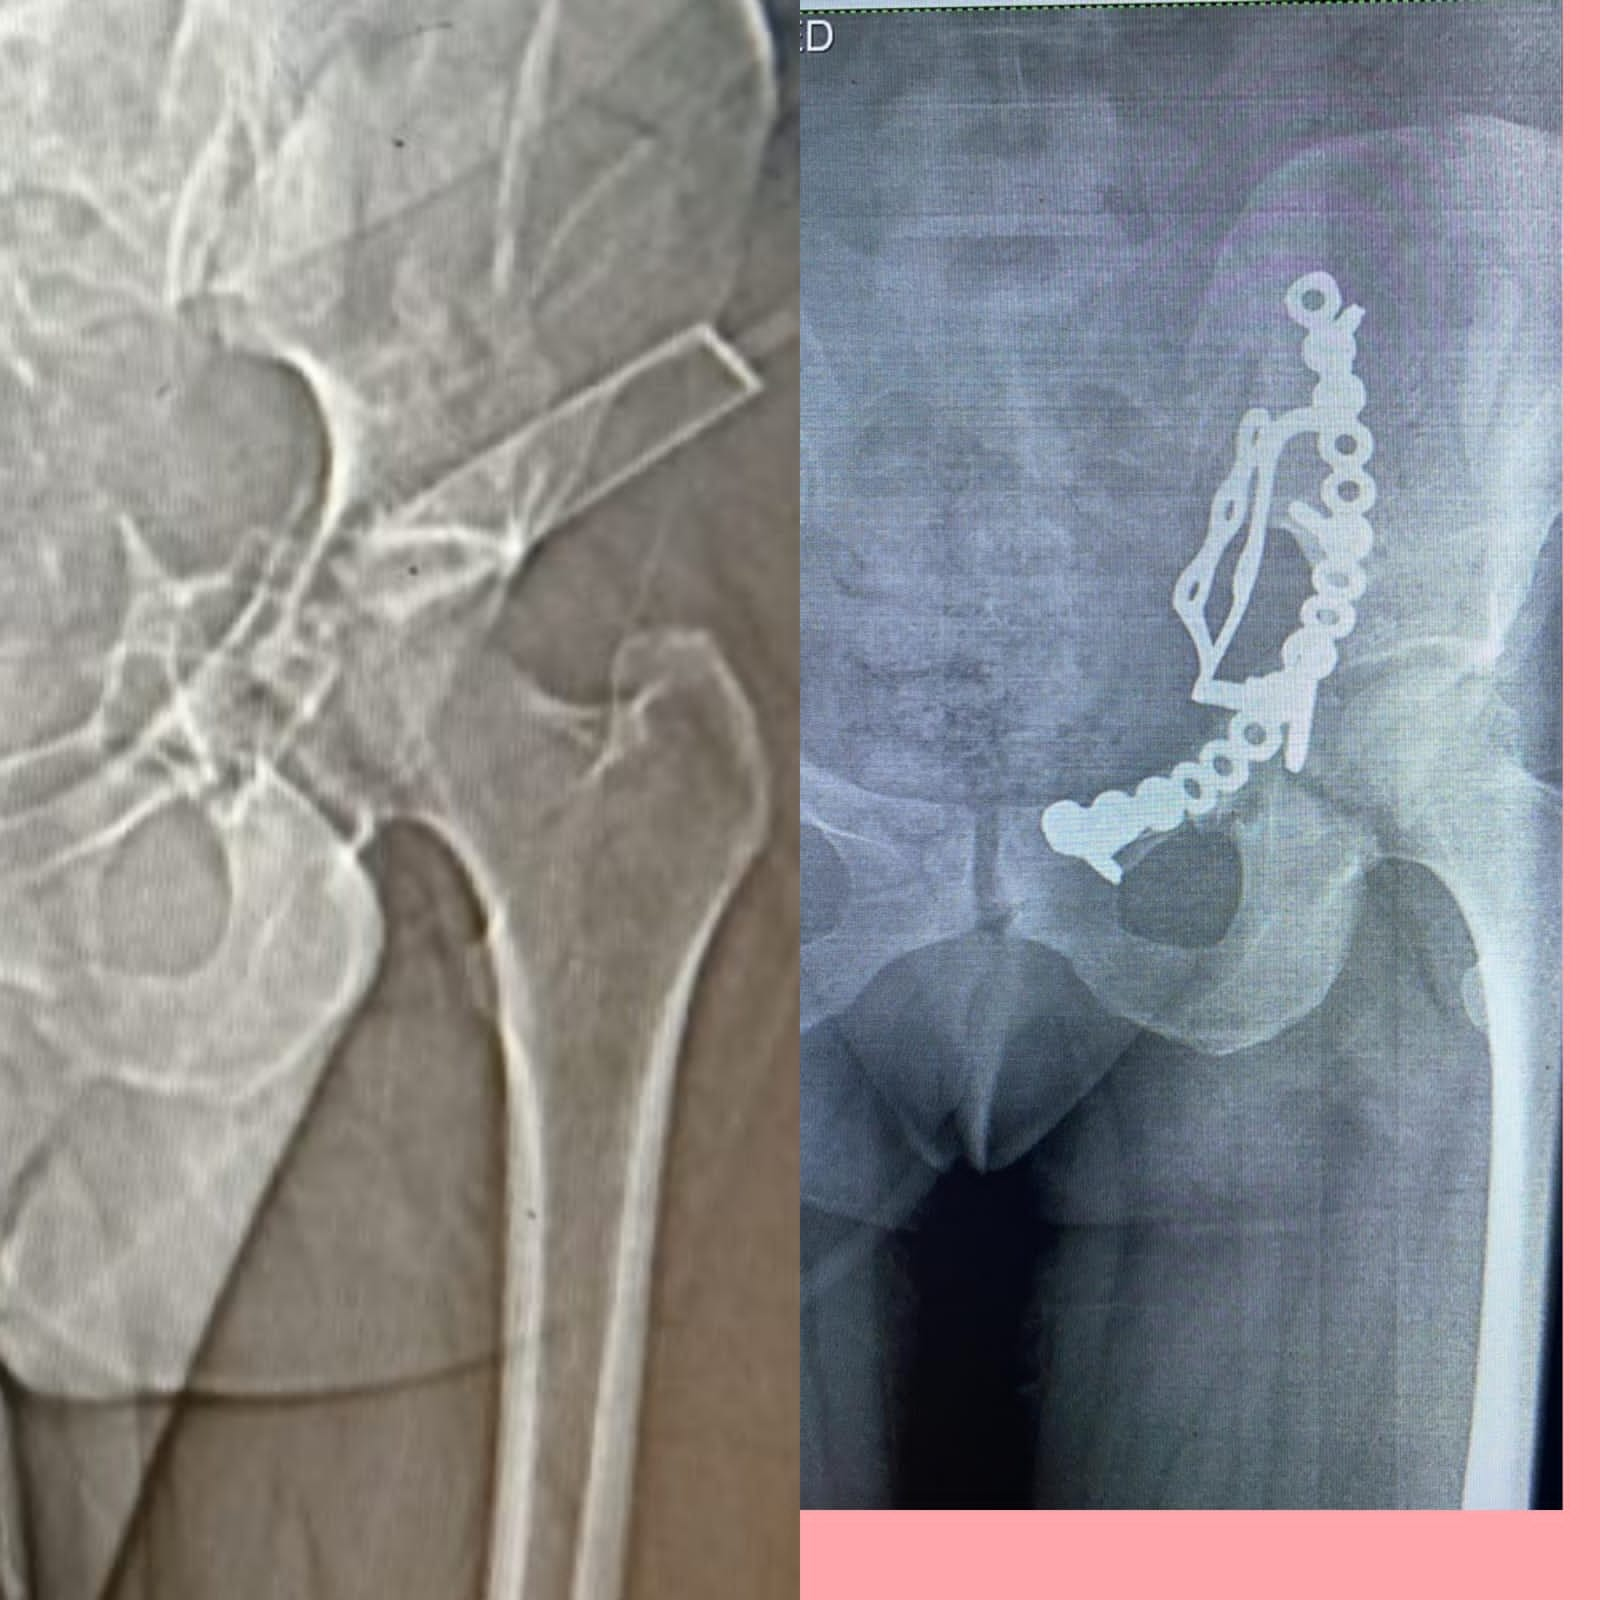

قام الفريق الطبي بقسم جراحة العظام بمستشفي أبوحماد المركزي، تحت إشراف مدير المستشفى، بإجراء عملية رد مفتوح مع تثبيت داخلي لكسر مفتت بالحق الحرقفي لعظم الحوض لسيدة، من خلال جراحة فتح البطن والحوض باستخدام شريحة من نوع خاص تحت مخدر عام بالعمليات...

تعد العملية ذات طابع خاص، وذلك بعد دخول المريضة قسم الإستقبال والطوارئ، إثر ادعاء حادث مروري، حيث تم إجراء كافة الفحوصات اللازمة وتبين اصابة المريضة بجرح بالمثانة نتج عنه بول دموي ووجود كسر مفتت بالحق الحرقفي لعظم الحوض، والمريضة الآن في حالة جيدة ومستقرة تحت متابعة الأطباء بالمستشفى...